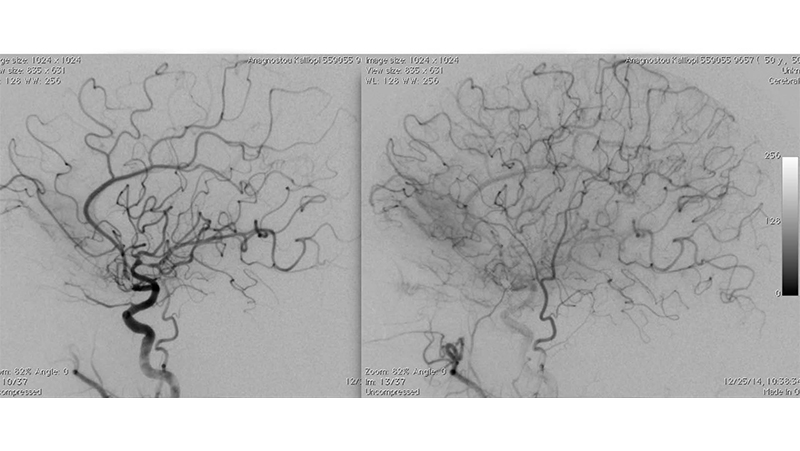

Εικόνα 3: Αγγειογραφία της αριστερής έσω καρωτίδος σε προσθιοπίσθια και πλάγια προβολή: Διακρίνεται η απόφραξη του τέλους του Μ1 τμήματος της μέσης εγκεφαλικής αρτηρίας.